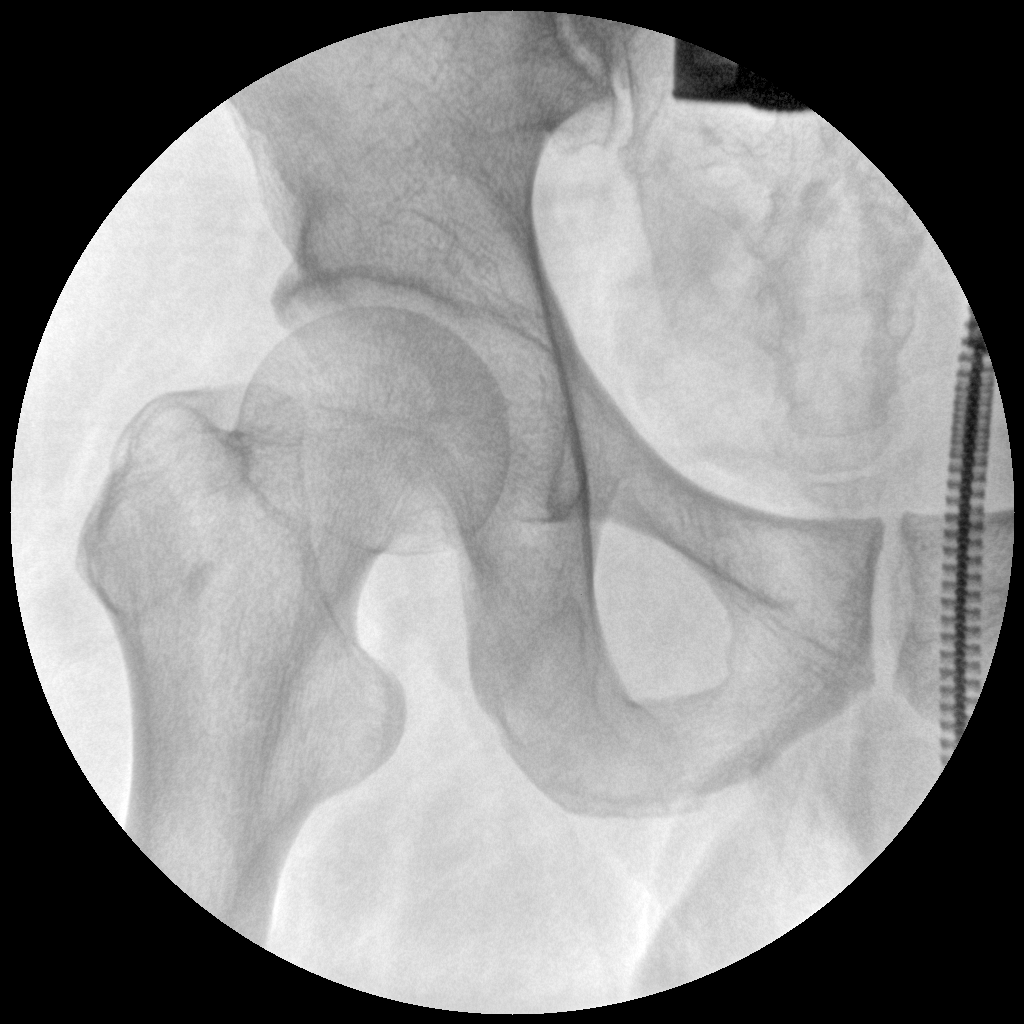

PLX112C 系列高频移动式手术X射线机

手术导航定位系统

●经典图文工作站,搭配双监双控,操作更自如●全数字化百万像素影像系统,图像清晰●独特的电动辅助支撑臂设计, 临床操作轻松自如●具备多种工作模式,满足更多临床需求●人体图形化触摸屏设计,操作方便快捷